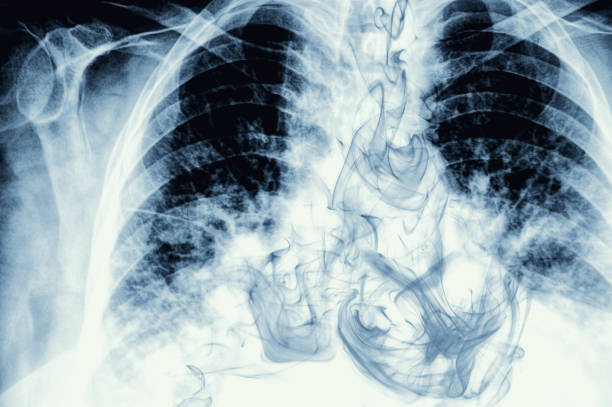

폐암 초기증상과 예방 알아보기

폐암 원인은 다양하지만 유전적 요인, 환경적 요인, 흡연 등이 있는 것으로 알려져 있으며 가족력이 특히 중요해 가족력이 있는 경우 꾸준한 관리가 중요합니다. 또한, 폐암의 대표적인 병인으로서 흡연은 직간접적인 영향이 강하여 폐암의 병인과 떼려야 뗄 수 없는 중요한 것으로 여겨집니다.